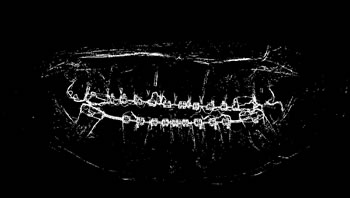

Determining ROI

For each image, after the annotation of the teeth, the buccal region was also annotated, covering the whole region delineated by the contour of the jaws. This process was carried out in view of preserving the area containing all the teeth (objects of interest). Finally, the region of interest (ROI) was determined by multiplying the values of the pixel array elements, representing the original panoramic X-ray image, by its corresponding binary matrix, resulting from the process of oral annotation. Figure 5 illustrates the whole process to determine the ROI of the images.